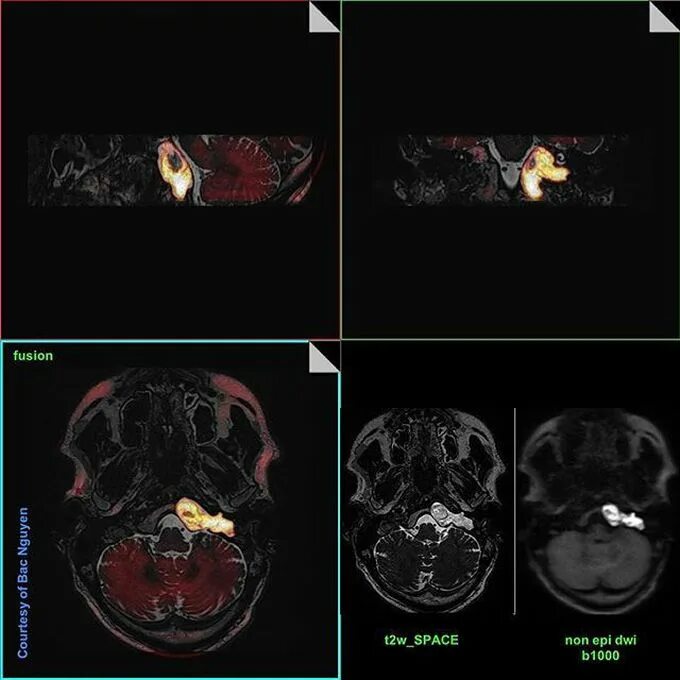

Мрт височных костей в режиме dwi